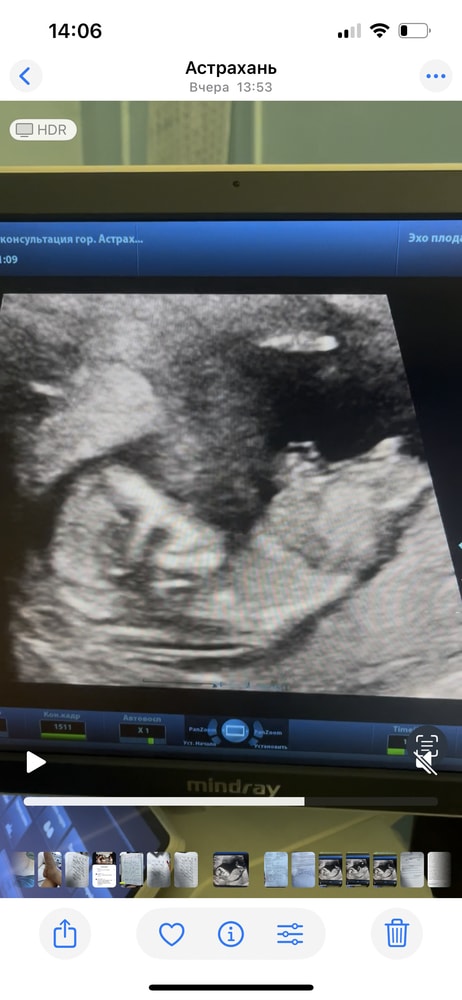

Я бы сказала девочка - половой бугорок вроде параллелен позвоночнику.

Тут вообще не сразу сообразишь, что есть что)) Но если то что я вижу - половой бугорок - девочка, скорее всего.

ну вот если на УЗИ это половой бугорок виден,то похоже девочка